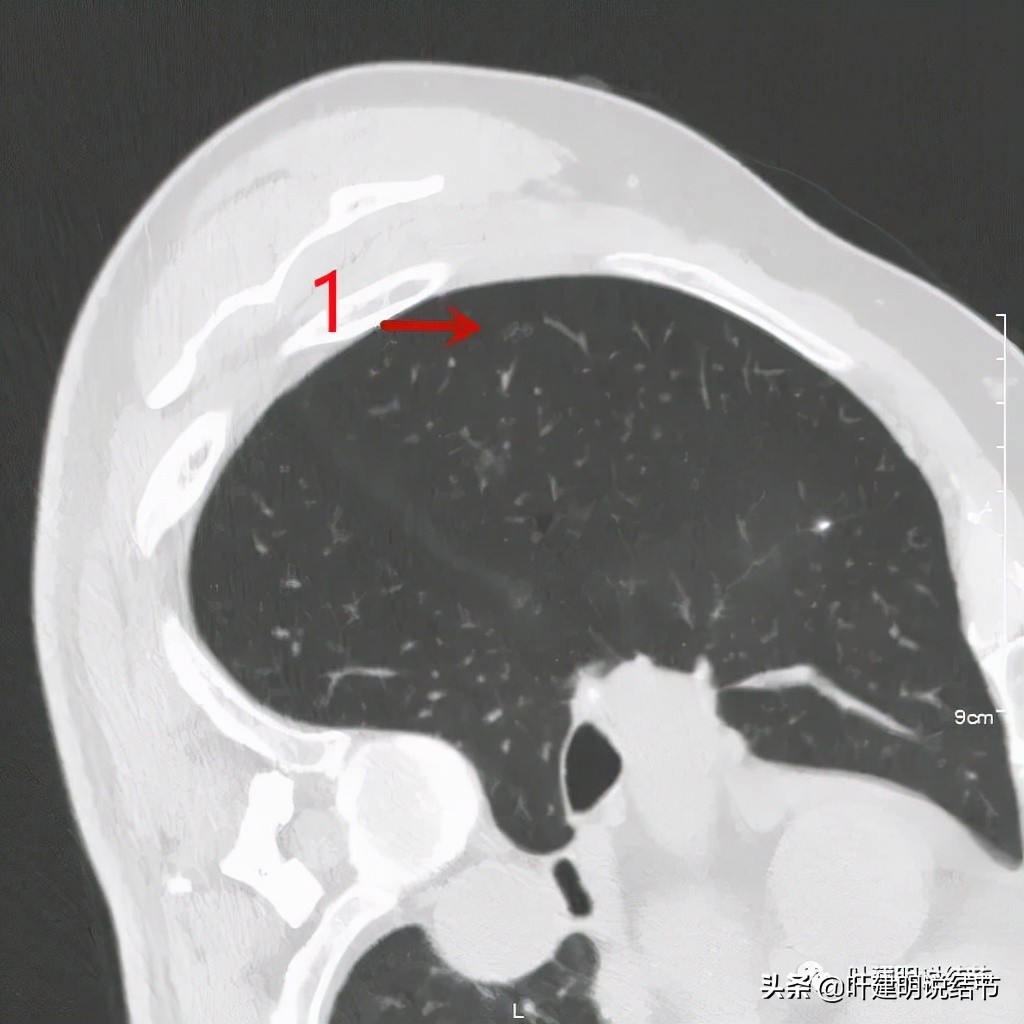

右侧病灶1:微小磨玻璃结节,考虑最多不典型增生